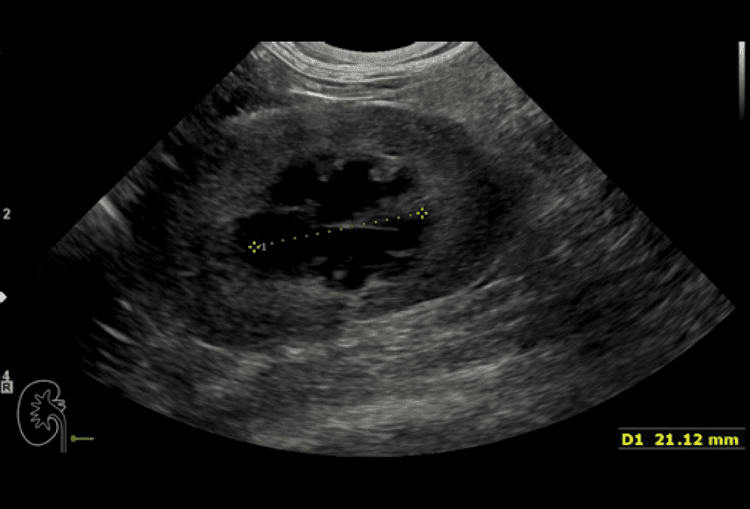

Un caso di idronefrosi bilaterale in un gatto che ha comportato l’applicazione di subcutaneous ureteral bypass supporta la consapevolezza dell’importanza della diagnosi precoce di malattia renale al fine di valutare al meglio come poter intervenire per rallentarne la progressione.

La diagnosi precoce è sempre più un imperativo in nefrologia. In questo articolo il dott. Claudio Brovida ha illustrato alcuni nuovi marcatori biologici che possono aiutare nella diagnostica differenziale in corso di nefropatia.